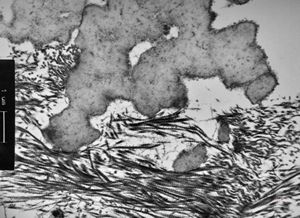

M,66y. | follicular cyst with hyaline Rushton bodies